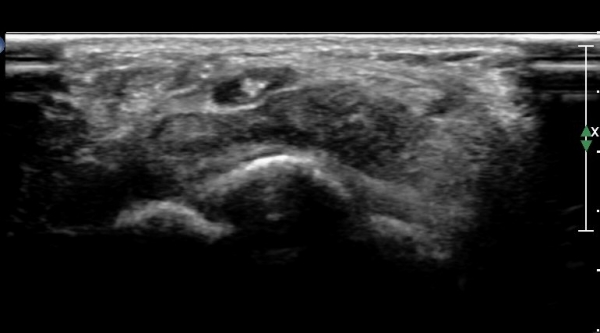

¼ö±Ù°ü ±ÙÀ§ºÎ Ⱦ´Ü¸é°Ë»ç¿¡  ƯÀÌ ¼Ò°ß º¸ÀÌÁö ¾Ê´Â´Ù(»çÁø 2)